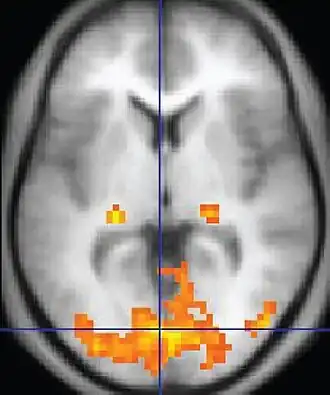

A fMRI scan showing regions of activation in orange, including the primary visual cortex (V1, BA17)

Functional MRI (fMRI) measures signal changes in the brain that are due to changing neural activity. It is used to understand how different parts of the brain respond to external stimuli or passive activity in a resting state, and has applications in behavioral and cognitive research, and in planning neurosurgery of eloquent brain areas.[48][49] Researchers use statistical methods to construct a 3-D parametric map of the brain indicating the regions of the cortex that demonstrate a significant change in activity in response to the task. Compared to anatomical T1W imaging, the brain is scanned at lower spatial resolution but at a higher temporal resolution (typically once every 2–3 seconds). Increases in neural activity cause changes in the MR signal via T*

changes;[50] this mechanism is referred to as the BOLD (blood-oxygen-level dependent) effect. Increased neural activity causes an increased demand for oxygen, and the vascular system actually overcompensates for this, increasing the amount of oxygenated hemoglobin relative to deoxygenated hemoglobin. Because deoxygenated hemoglobin attenuates the MR signal, the vascular response leads to a signal increase that is related to the neural activity. The precise nature of the relationship between neural activity and the BOLD signal is a subject of current research. The BOLD effect also allows for the generation of high resolution 3D maps of the venous vasculature within neural tissue.